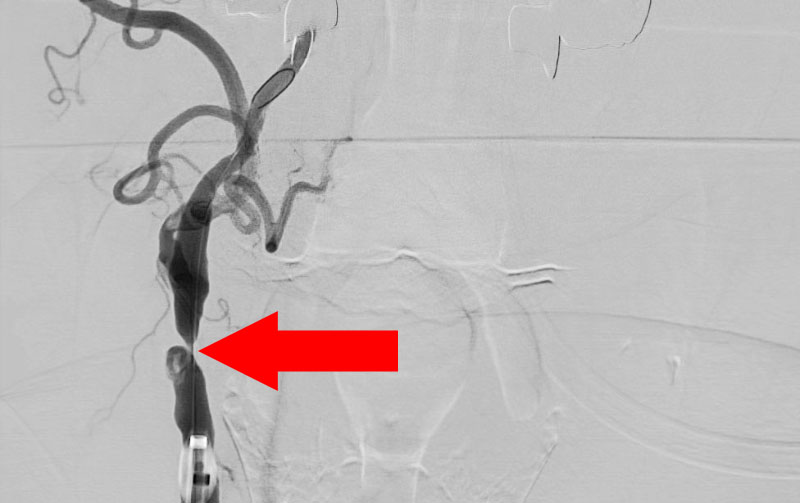

No.1377 手術前

No.1377 手術中

No.1377 手術後